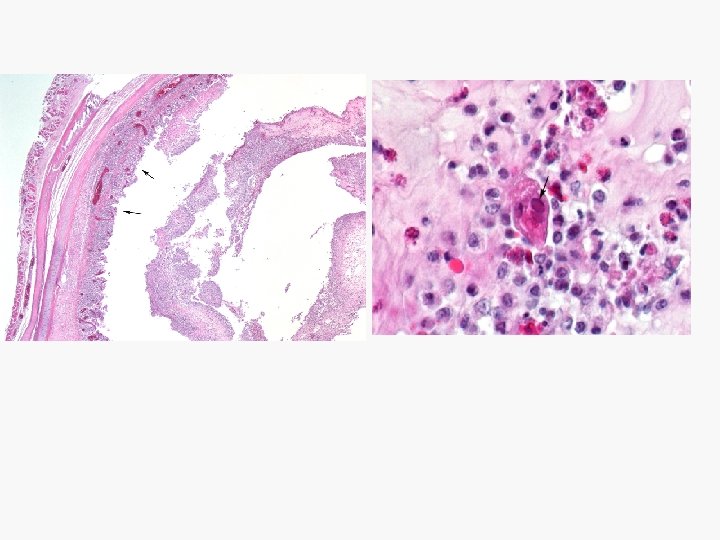

3 Those affect the posterior one third Cause: Eimeria burntti and Eimeria tenella Gross pathology: q Presence of caseous or cheesy cores in the cecum. q Marked typhlitis. q Blood appear in ceca and feces in early cases.